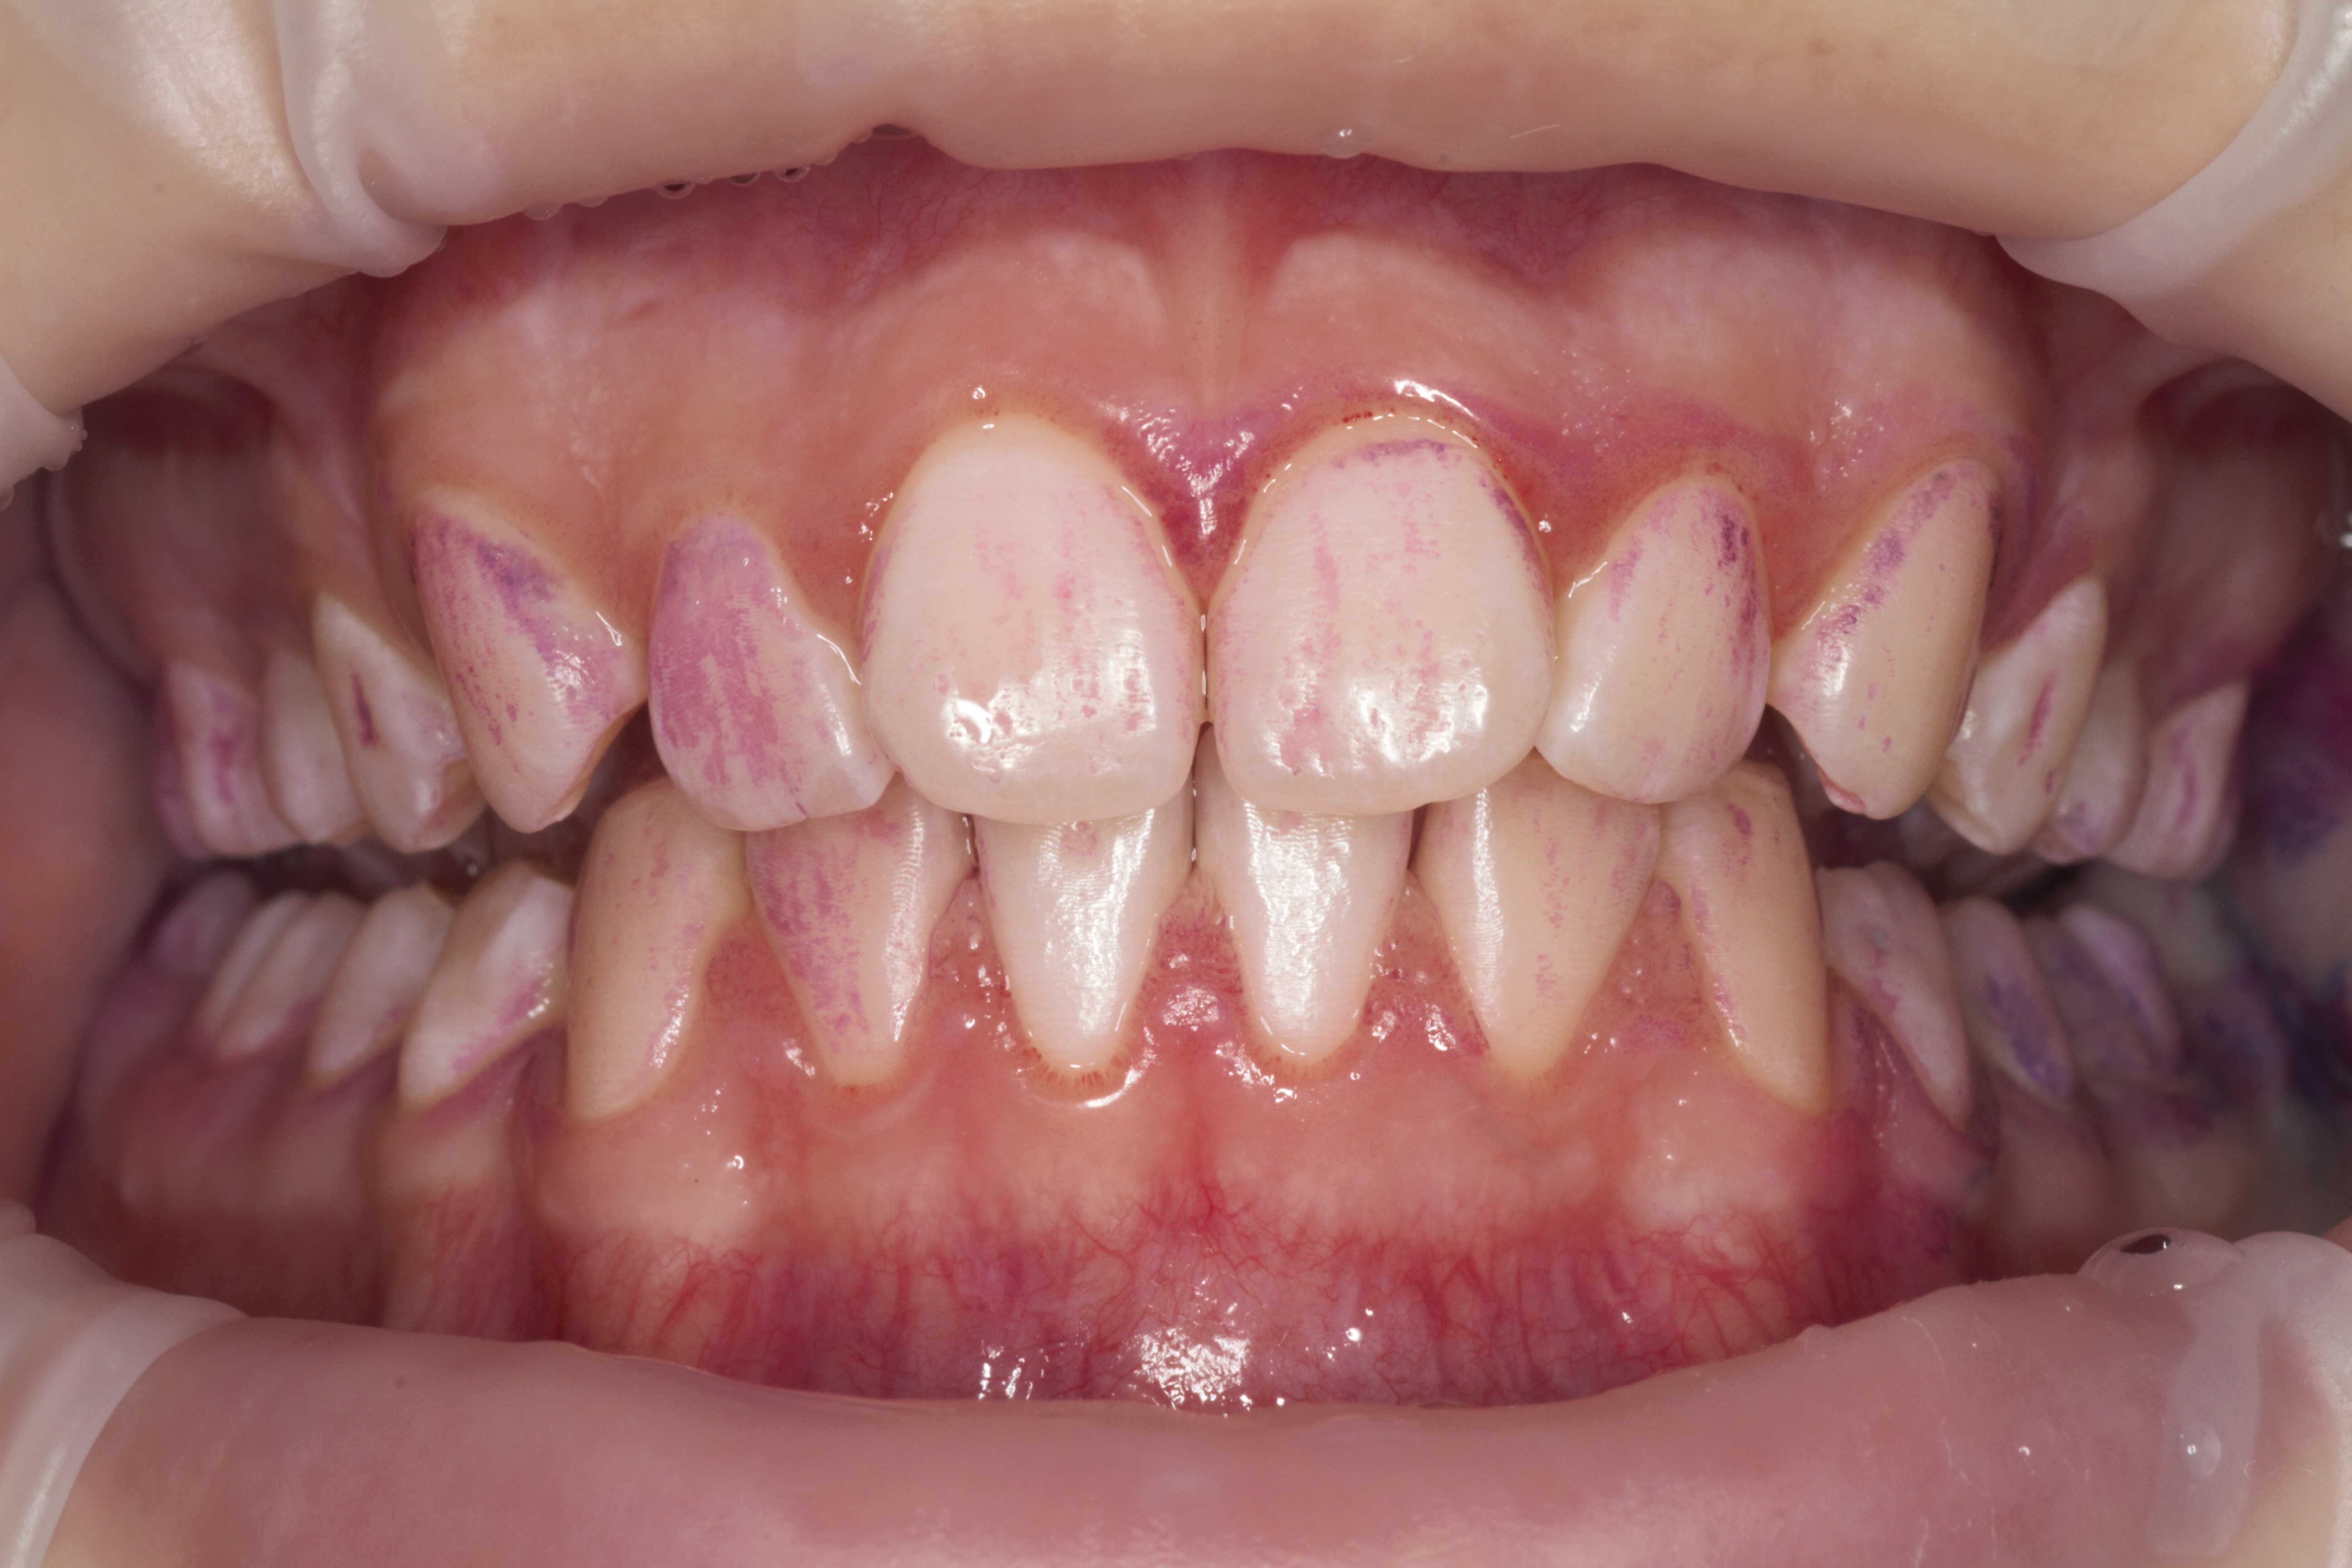

- Проведение профессиональной гигиены полости рта по GBT-протоколу на аппарате AIRFLOW® PROPHYLAXIS MASTER

- Эстетическая реставрации жевательной и фронтальной группы зубов современными пломбировочными материалами, диагностика кариеса на ранних этапах развития, предупреждение образования вторичного кариеса в области запломбированных зубов